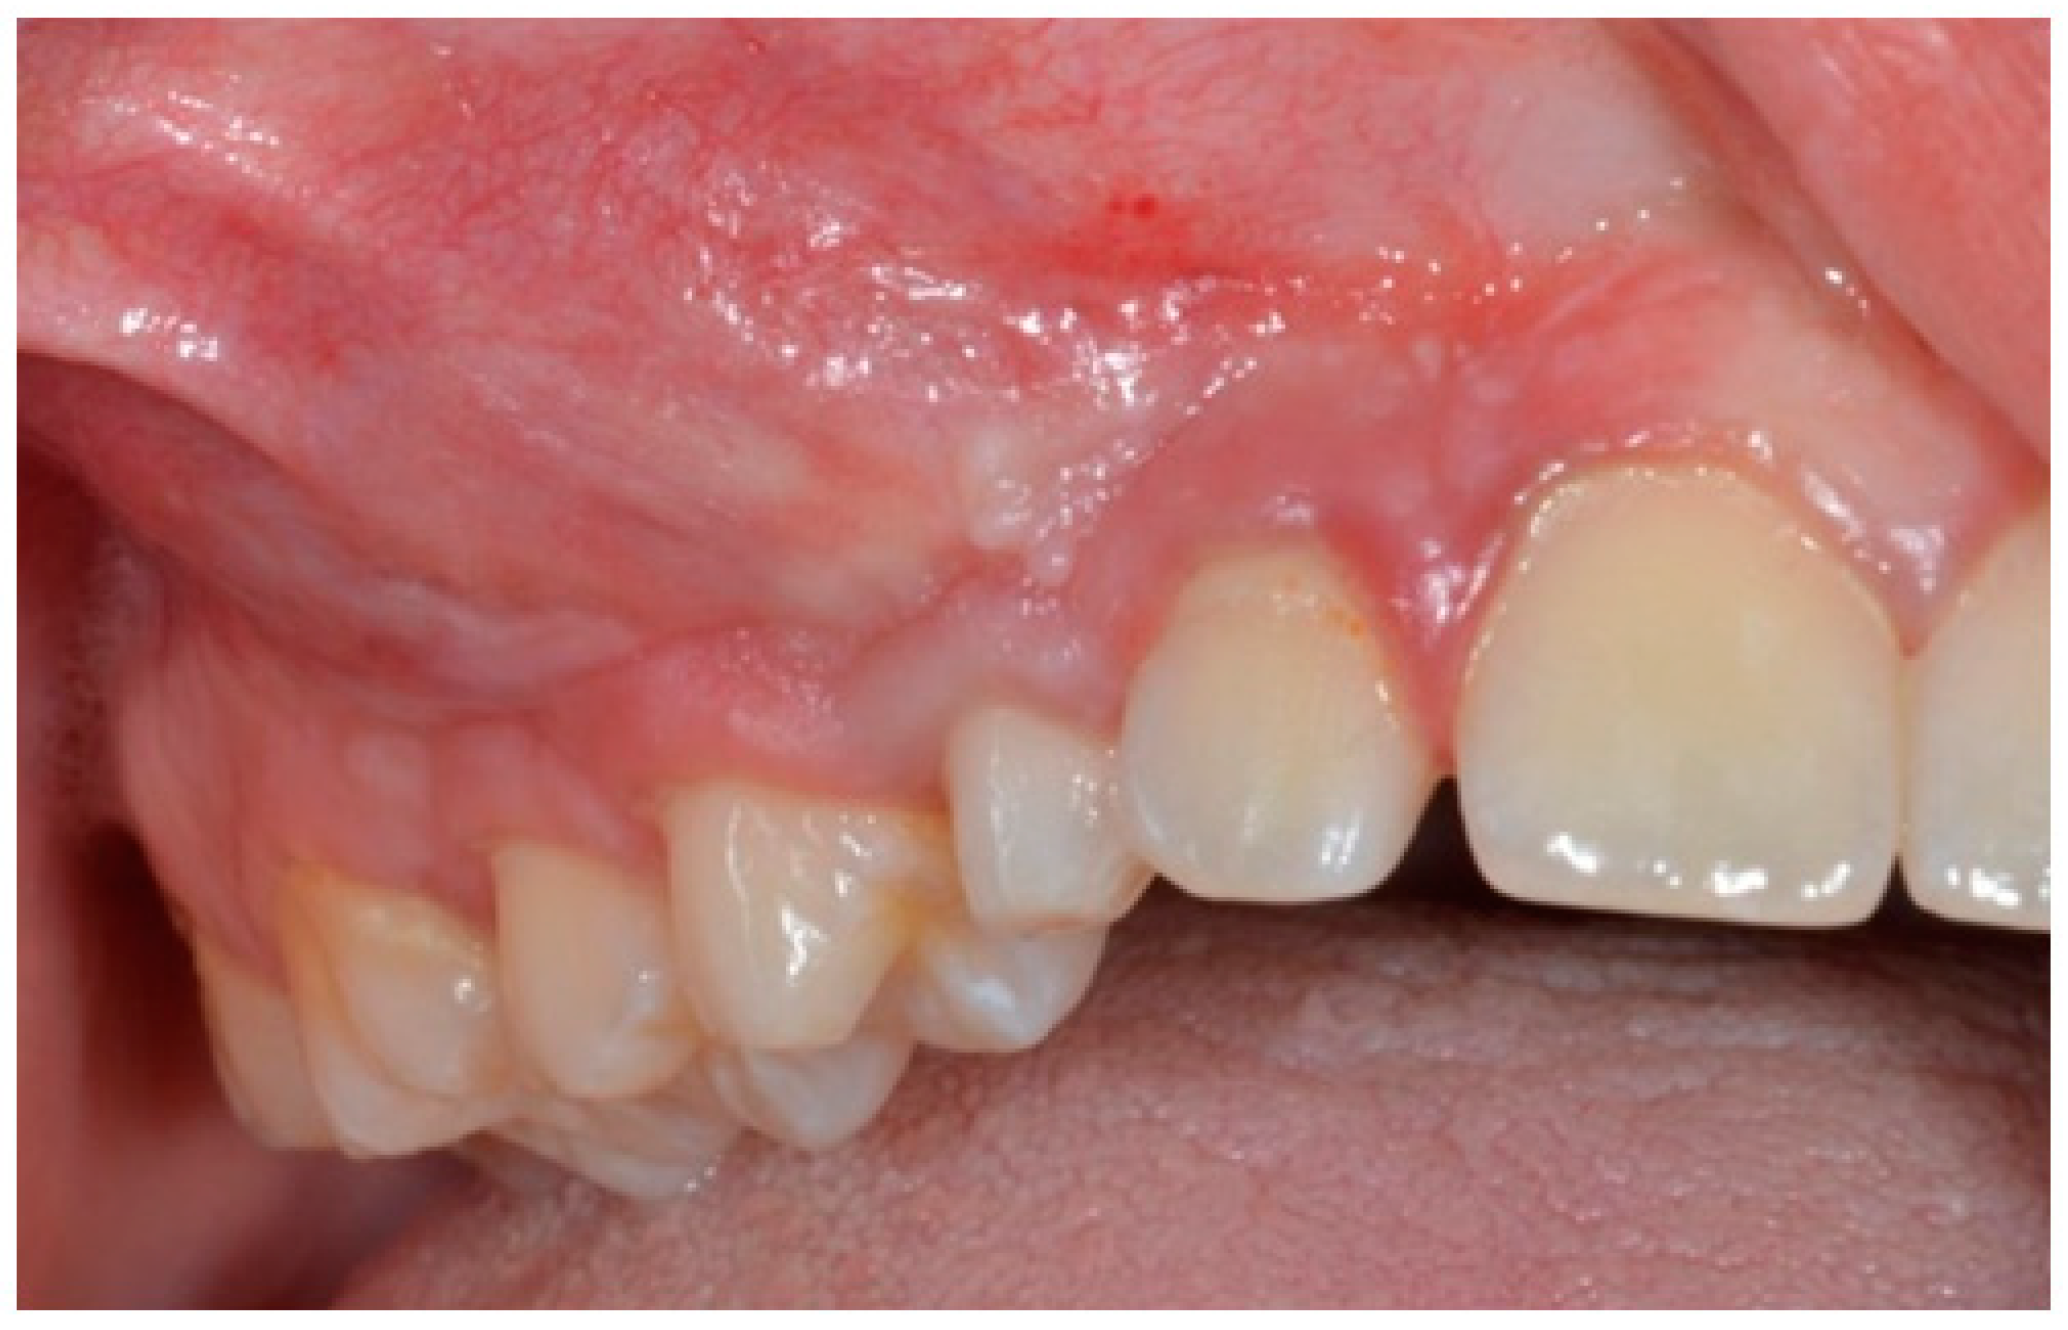

The AOT case refers to 2018 when a 14-year-old male patient was referred to the Department of Oral and Maxillo-Facial Sciences of the Sapienza University of Rome with pain and swelling in the right maxilla. Clinical examinations showed a single 4 × 4 cm swelling on the labial aspect of the right maxillary alveolus in relation to teeth 12 to 17. The overlying mucosa was normal (Figure 1). On palpation, the swelling was bony, hard and non-tender. Radiographic examinations such as panoramic X-ray and computed tomography scan (Figure 2) showed a demarcated unilocular radiolucent lesion extending from 1.2 to 1.7 with a permanent canine embedded within the lesion and pushed away from its normal position. The possibilities of follicular cyst or odontogenic tumor were considered clinically.

Figure 1. Expansion of buccal cortical bone.